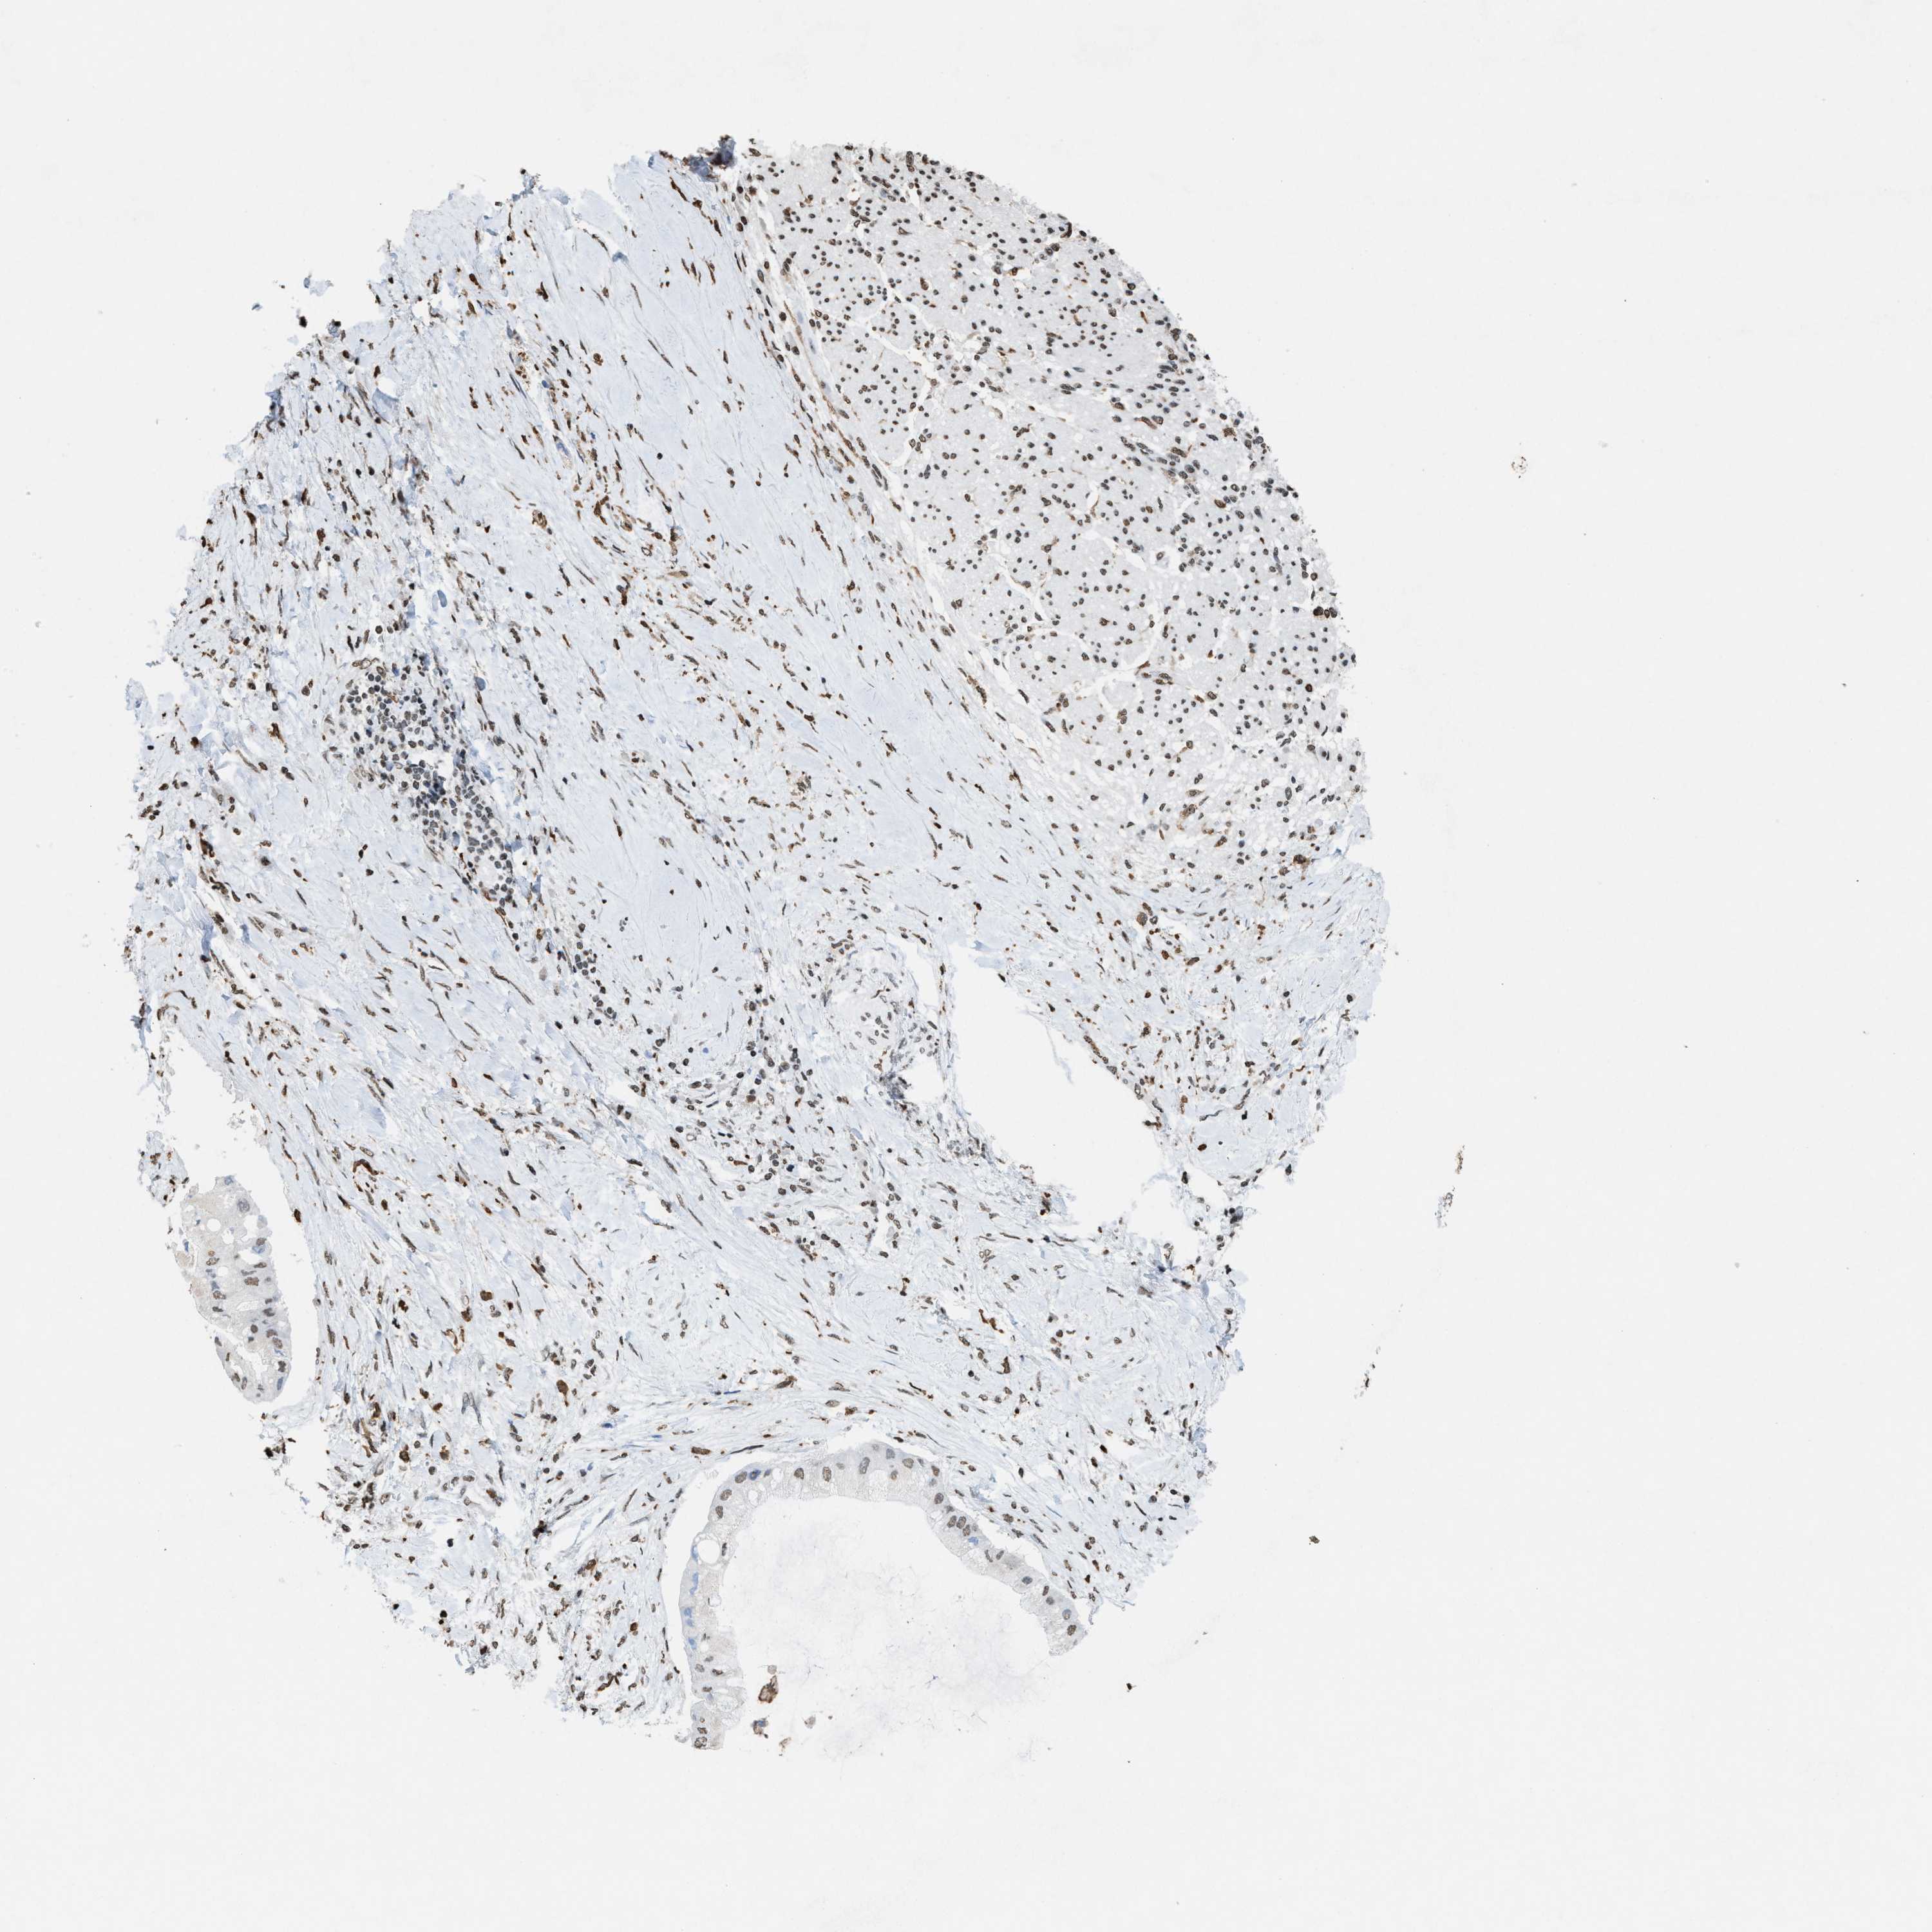

LIVER CANCER - Protein expressioni

A mouse-over function shows sample information and annotation data. Click on an image to view it in a full screen mode. Samples can be filtered based on level of antibody staining by selecting one or several of the following categories: high, medium, low and not detected. The assay and annotation is described here.

Note that samples used for immunohistochemistry by the Human Protein Atlas do not correspond to samples in the TCGA dataset.

Antibody stainingi

Antibody staining in the annotated cell types in the current human tissue is reported as not detected, low, medium, or high, based on conventional immunohistochemistry profiling in selected tissues. This score is based on the combination of the staining intensity and fraction of stained cells.

Each image is clickable and will lead to virtual microscopy that enables deeper exploration of all samples and also displays staining intensity scores, fraction scores and subcellular localization as well as patient and tissue information for each sample.

Antibody HPA021816

Antibody CAB002209

Staining

High

Medium

Low

Not detected

Intensity

Strong

Moderate

Weak

Negative

Quantity

>75%

75%-25%

<25%

None

Location

Nuclear

Cytoplasmic/membranous

Cytoplasmic/membranous,nuclear

Cholangiocarcinoma

Carcinoma, Hepatocellular, NOS